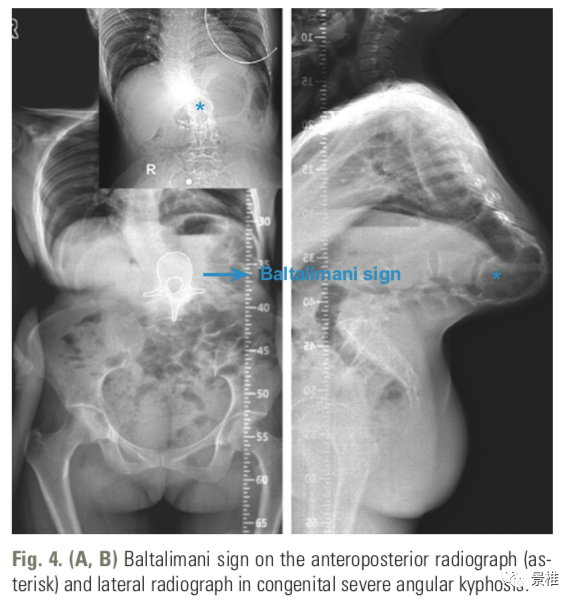

土耳其伊斯坦布尔xxx Baltalimani骨病医院的学者发现了一个脊柱严重角状后凸(≥90°)正位X线片的影像学征象,将其命名为 Baltalimani征

土耳其伊斯坦布尔xxx Baltalimani骨病医院的学者发现了一个脊柱严重角状后凸(≥90°)正位X线片的影像学征象,将其命名为 Baltalimani征。

Baltalimani征阳性:脊柱严重角状后凸(SAK)的顶椎相邻椎体处于垂直翻转状态。在正位x线片上可以观察到椎体轮廓呈轴位观。

Baltalimani征阳性的正侧位X片示例。这种严重成角压迫使得脊髓损伤发生几率比阴性征象增加了61.9%

相较于先天性脊柱后凸,脊柱结核和神经纤维瘤病患者所致脊柱后凸的病程进展更快,出现Baltalimani征时更易发生神经功能障碍。